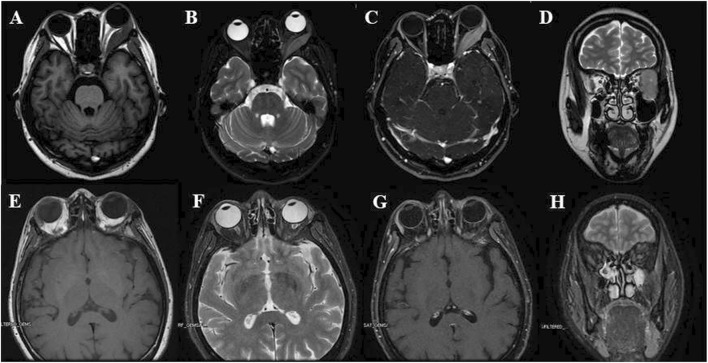

髓样肉瘤(MS)是由原始或幼稚的髓样细胞在骨髓外形成。它主要发生在软组织/结缔组织和皮肤,很少累及眼眶。我们报告了两名女性成人的病例,分析了临床病理特征,并回顾了相关文献。两名患者的平均年龄为 28 岁,均表现为单侧突眼,患眼伴有不同程度的视力受损和眼球活动受限。尽管如此,他们的整体健康状况良好,没有明显的家族病史。不过,患者没有急性髓性白血病(AML)的全身临床表现。两名患者都接受了眼眶肿瘤的手术切除。免疫组化结果显示,CD43、白细胞共同抗原(LCA)和髓过氧化物酶(MPO)染色阳性,Ki67染色也呈高度阳性,可诊断为多发性硬化症。骨髓细胞学检查未发现明显异常。第一例患者接受了术后化疗、局部放疗和异基因造血干细胞移植(allo-HSCT),第二例患者接受了辅助化疗和放疗。两位患者在随访期间(一位超过 5 年,另一位超过 10 年)均未发现复发或转移。眼眶多发性硬化症并不常见,临床和影像学表现也不典型。诊断取决于病理形态学和免疫组化染色,术后辅助化疗、局部放疗和同种异体造血干细胞移植预后良好。

Myeloid sarcoma (MS) occurs when primitive or naive myeloid cells form outside the bone marrow. It occurs mainly in soft/connective tissue and skin; orbital involvement is rare. We report the cases of two female adults, analyze the clinicopathologic characteristics, and review the literature. The average age of both patients was 28 years and they presented unilateral proptosis combined with varying degrees of impaired visual acuity and restricted ocular motility in the affected eye. Despite this, they maintained good overall health and no notable family history. However, the patients had no systemic clinical manifestations of acute myeloid leukemia (AML). Both patients underwent surgical resection of the orbital tumor. Immunohistochemistry showed positive staining for CD43, Leukocyte Common Antigen (LCA), and myeloperoxidase (MPO) and a high level of positive staining for Ki67, which were diagnostic for MS. Bone marrow cytology examination showed no apparent abnormalities. Postoperative chemotherapy, local radiotherapy, and allogeneic hematopoietic stem cell transplantation (allo-HSCT) were performed in Case 1, while the second patient underwent adjuvant chemotherapy and radiotherapy. No recurrence or metastasis was found in either patient during follow-up (one more than 5 years, the other more than 10 years). The occurrence of orbital MS is infrequent, with atypical clinical and imaging findings. The diagnosis depends on pathomorphology and immunohistochemical staining, and the prognosis is good with postoperative adjuvant chemotherapy, local radiotherapy, and allo-HSCT.